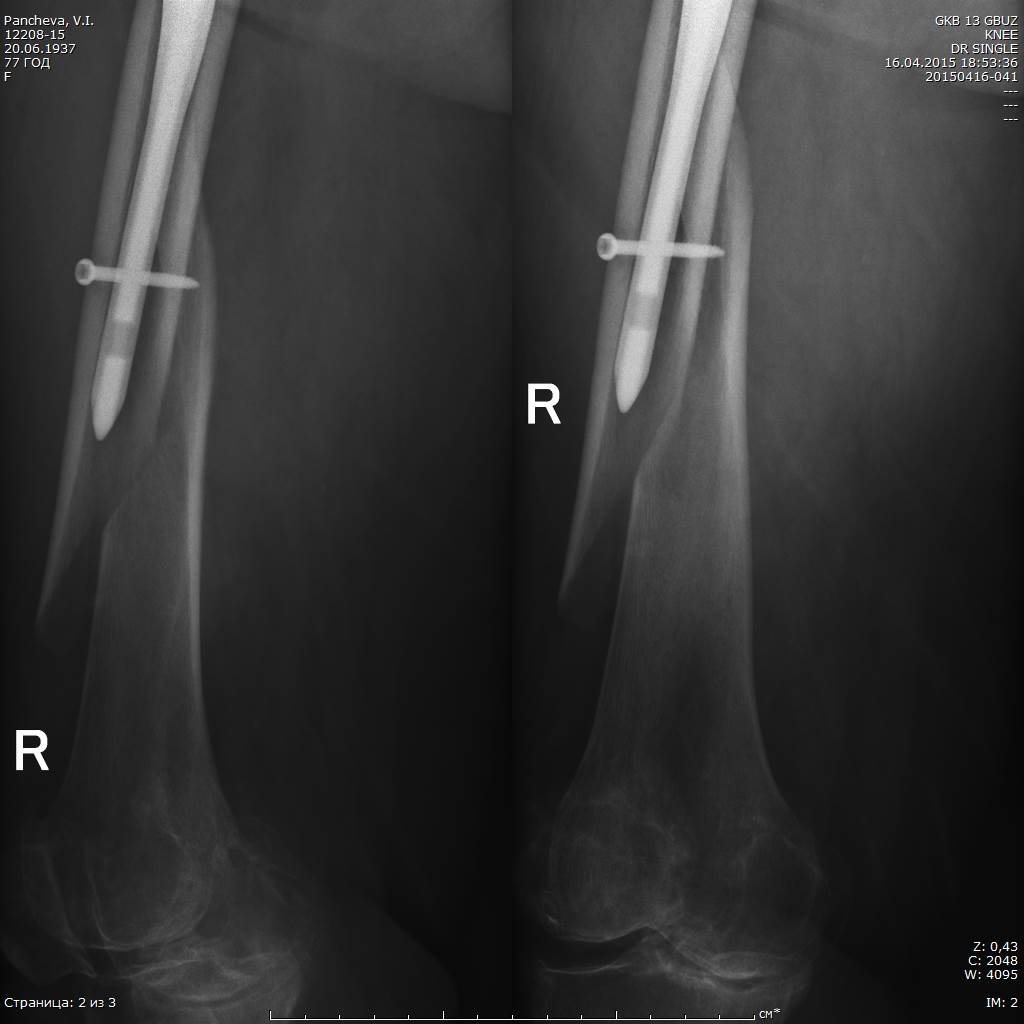

Имя     : 20150416-041_DR SINGLE _1.jpg

Имя     : 20150416-041_DR SINGLE _2.jpg